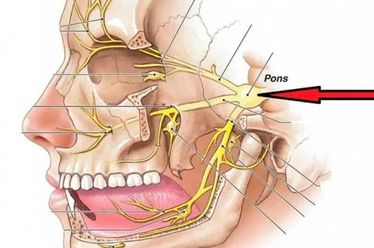

O sintoma mais clássico é a dor na região lombar que irradia para a perna, conhecida como ciatalgia, podendo chegar até o pé. Além da dor, o paciente pode sentir formigamento, dormência e, em casos mais graves, perda de força muscular na perna afetada. É fundamental procurar um neurocirurgião se a dor for persistente ou vier acompanhada de alterações de sensibilidade ou força.

A intervenção cirúrgica é reservada para casos específicos: quando o tratamento conservador não apresenta resultados após semanas ou meses, se a dor for incapacitante, ou se houver sinais de dano neurológico progressivo, como perda de força significativa ou alterações no controle da bexiga e intestino (Síndrome da Cauda Equina), que é uma urgência médica.